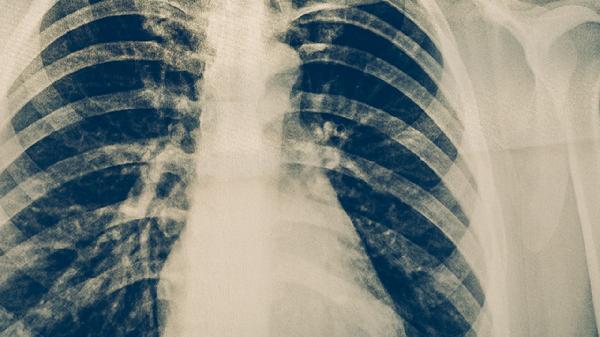

细菌性支气管肺炎主要由肺炎链球菌、流感嗜血杆菌、金黄色葡萄球菌、卡他莫拉菌和肺炎克雷伯菌等病原体感染引起。发病与免疫力下降、呼吸道防御机制受损、慢性基础疾病、环境刺激及病原体毒力增强等因素相关。